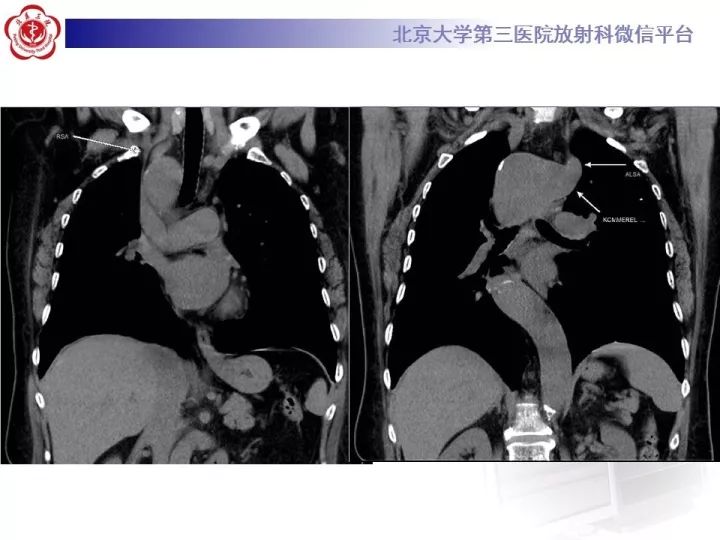

【病例】右位主动脉弓合并迷走左锁骨下动脉1例CT